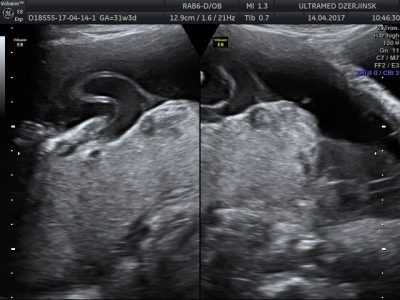

Первородящая Щ., 26 лет (репродуктивный анамнез не отягощен), обратилась для планового осмотра в рамках раннего пренатального скрининга в сроке 12 +6 нед. Сканирование проводилось при трансабдоминальном и трансвагинальном доступе. При эхографии выявлено: размеры плода соответствовали сроку гестации: КТР плода 62 мм, БПР 18 мм, ОЖ 60 мм, толщина воротникового пространства 1,8 мм, длина носовой кости 2,3 мм. ЧСС плода 157 в минуту, ритм правильный. Диаметр желточного мешка 6 мм. Плацента располагалась по передней стенке матки, без особенностей размеров и структуры. Прикрепление пуповины к плаценте центральное. Экзоцеломическая полость не определялась. При допплерометрии выявлено отсутствие диастолического компонента кровотока в d. venosus и пуповине. У плода выявлен асцит (рис. 1). Ультразвуковых данных о ВПР плода не обнаружено. На расстоянии 4 мм от передней брюшной стенки плода визуализировалось гетерогенное образование с четкими ровными контурами округлой формы диаметром 25 мм (рис. 1-4), связанное с пуповиной, сложной эхоструктуры, представленное анэхогенным толстостенным включением, окруженным линейными септами повышенной эхогенности. В режиме ЦДК в выявленном образовании пуповины регистрировались единичные цветовые локусы (рис. 3, 4).

Рис. 1. Гетерогенное образование, связанное с пуповиной, асцит. Парасагиттальное трансабдоминальное сканирование.